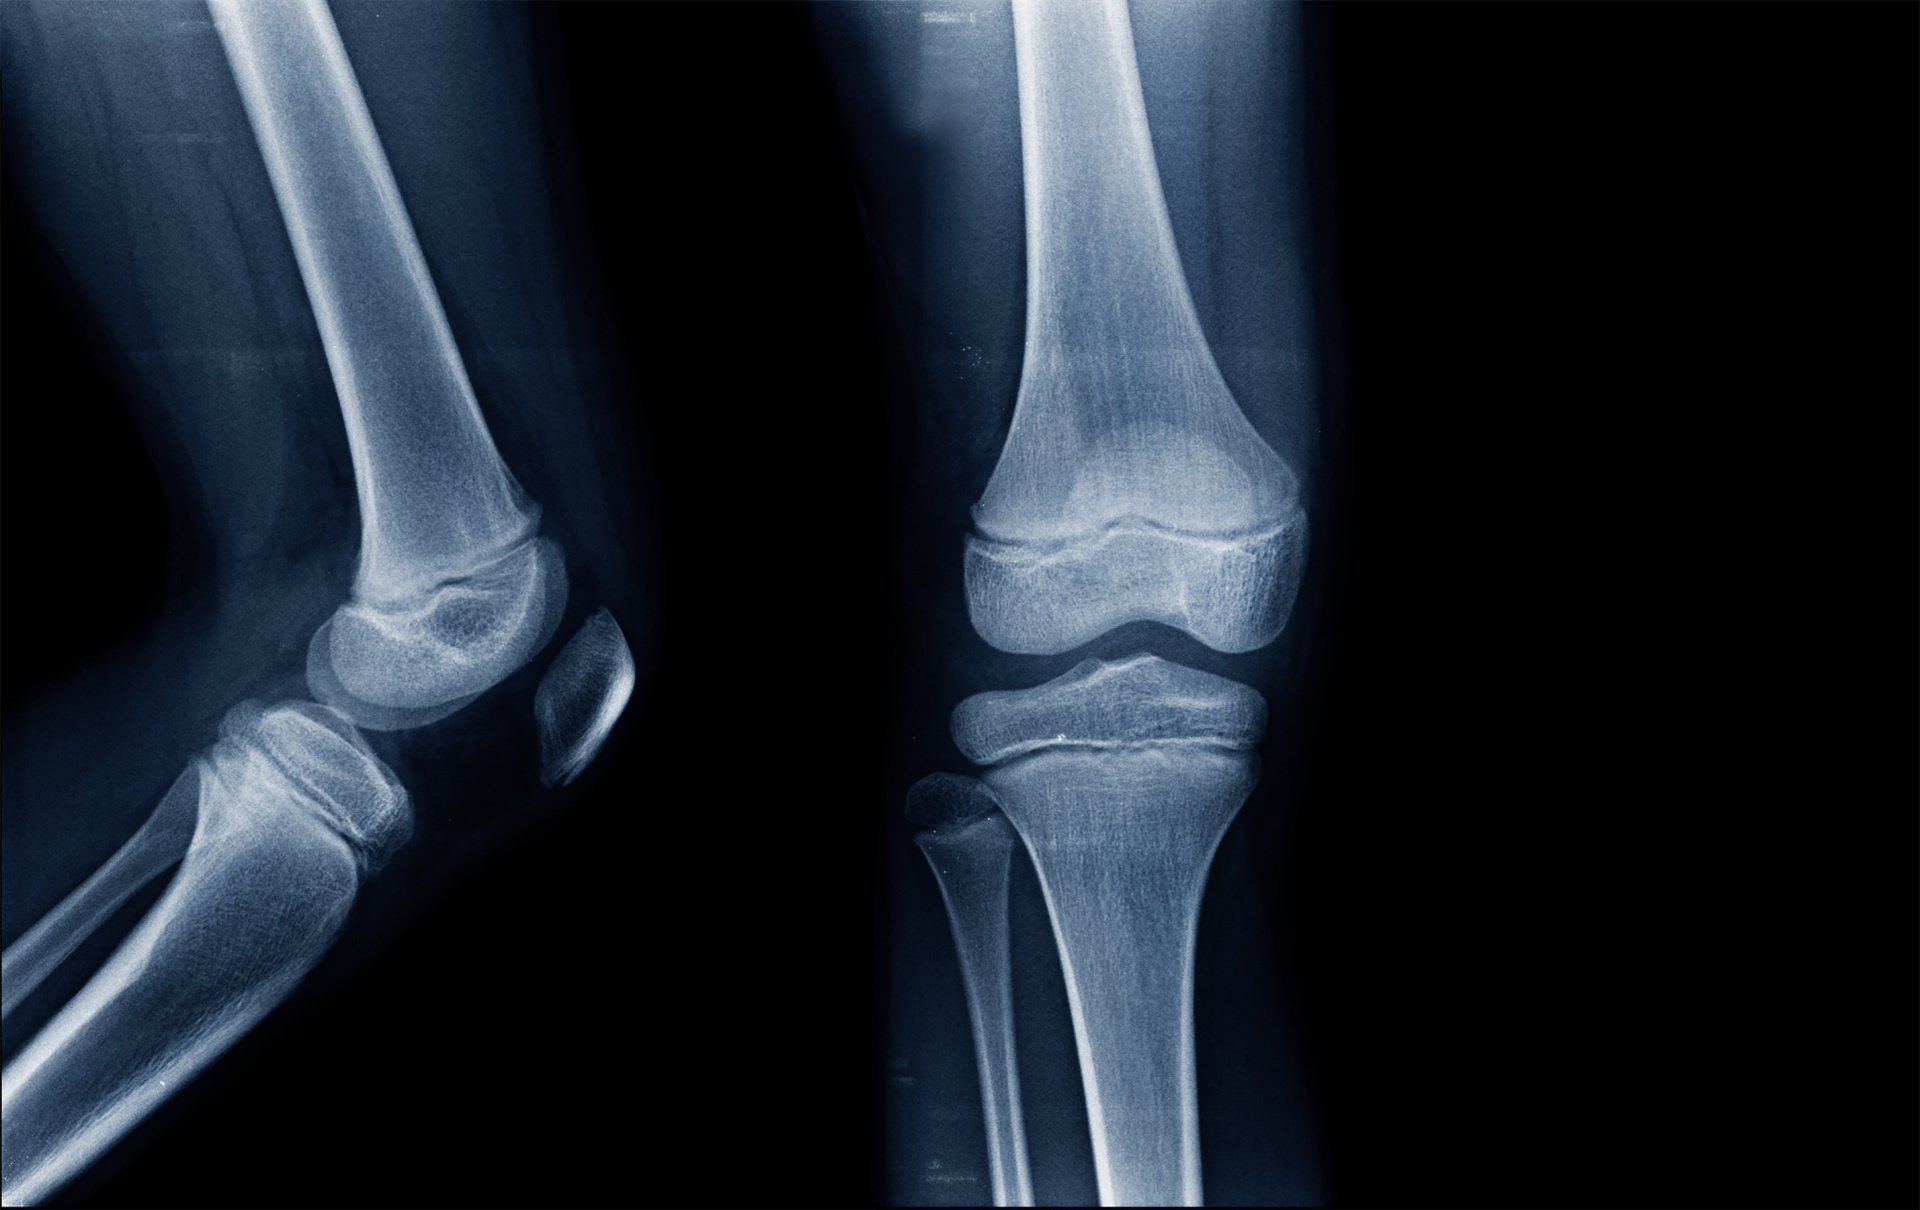

- Growth plate (also called physis) is the area of bone that allows it (and therefore the child) to grow in height

- Growth plates are present on either end of long bones (e.g. femur, tibia, humerus)

- Around the knee there are two growth plates:

- Distal femur (lower end of the thigh bone)

- Proximal tibia (upper end of shin bone)

- They are the softest and weakest part of a child’s growing skeleton as they lack calcium:

- As a result, they are seen on X-ray via the black line that crosses the bone parallel to the joint plane:

- presence of calcium is what makes bone appear white on X-ray so the lack of calcium in growth plates makes them look black

- X-ray and MRI scans are more difficult to interpret due to developmental variations from adults (e.g. presence of growth plates)